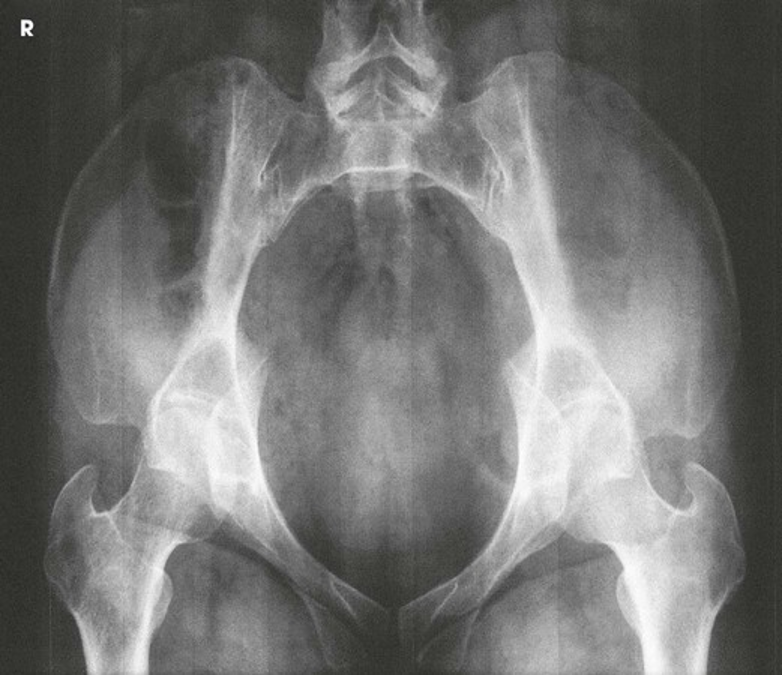

AP Projection; Pelvis and Proximal Femora (CR & SS)

The image shows an AP projection of the pelvis and of the head, neck, trochanters, and proximal one third or one fourth of the shaft of the femora

NOTE: 1st projection that you do in a pelvis/hip series.

NOTE: You can shield for a pelvis. It is best practices that we do

AP Projection; Pelvis and Proximal Femora (Eval Criteria)

• Evidence of proper collimation

• Entire pelvis along with the proximal femora

• Both ilia and greater trochanters equidistant to the edge of the radiograph

• Lower vertebral column centered to the middle of the radiograph

• No rotation of pelvis

o Both ilia symmetric in shape

o Symmetric obturator foramina

o Ischial spines equally seen

o Sacrum and coccyx aligned with the pubic symphysis

• Proper rotation of proximal femora

o Femoral necks in their full extent without superimposition

o Greater trochanters in profile

o Lesser trochanters, if seen, visible on the medial border of the femora

• Soft tissue and bony trabecular detail

Note: Rotate lower limbs 15 to 20 degrees internally. *Must include about ¼ or 1/3 of upper femurs